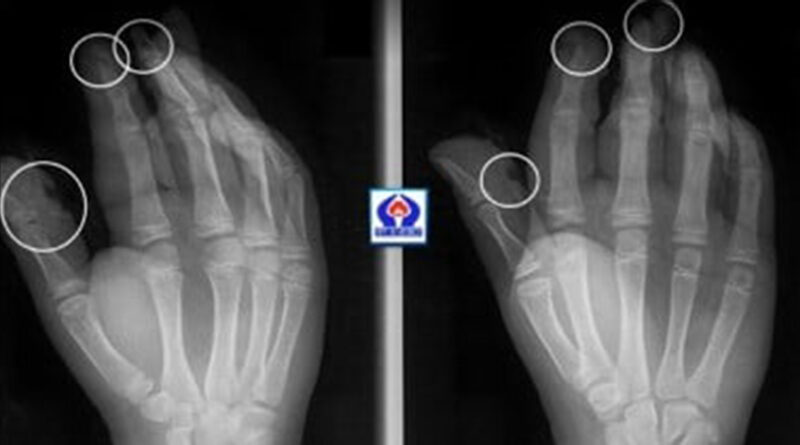

Երեխաներից երկուսի մոտ եղել են անդամահատված մատներ, ճայթուկը պայթել է հենց ձեռքերի մեջ, մյուս երկուսի մոտ համեմատաբար թեթև վնասվածքներ են եղել:

«Սուրբ Աստվածամայր» ԲԿ-ի պլաստիկ վիրաբույժների կողմից երեխաները վիրահատվել են և դուրս գրվել հիվանդանոցից: